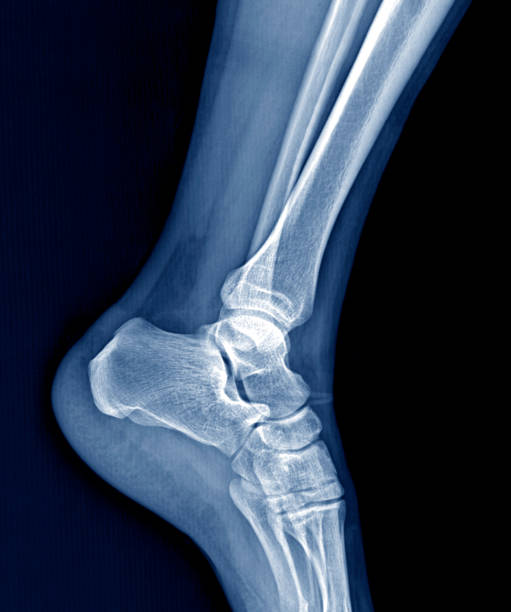

발뒤꿈치가 아픈 이유 2. 아킬레스건염

발뒤꿈치가 아픈 이유 두 번째는 아킬레스건염입니다. 아킬레스건염은 아킬레스건 부위가 반복적으로 미세한 손상을 입으면서 생기는 통증으로 이 역시 발뒤꿈치 통증을 유발합니다.

아킬레스건염 역시 뒤꿈치 혹은 발바닥에서 주로 통증이 느껴지며 특히 아킬레스건 부위가 부어오르며 움직임을 가져간 이후에는 종아리에서부터 발뒤꿈치까지 통증이 심하게 나타나고 이러한 증상이 지속되면 무플, 고관절, 허리에까지 무리가 갈 수 있기 때문에 족저근막염과 마찬가지로 빠른 치료를 받는 것이 중요합니다.

발뒤꿈치가 아픈 이유 5. 발목 터널 증후군

발뒤꿈치가 아픈 이유 다섯 번재는 발목 터널 증후군입니다. 내측 복사뼈와 발뒤꿈치 뼈 사이의 족근관을 관통하는 후경골 신경이 눌리거나 손상되면 저림, 작열감 등을 느끼게 됩니다. 이때는 신경 압박에 의한 통증이기 때문에 앞서 언급한 연조직 손상과 달리 통증의 위치가 명확하지 않고 신경 경로를 따라 퍼지는 특성을 갖고 있습니다.